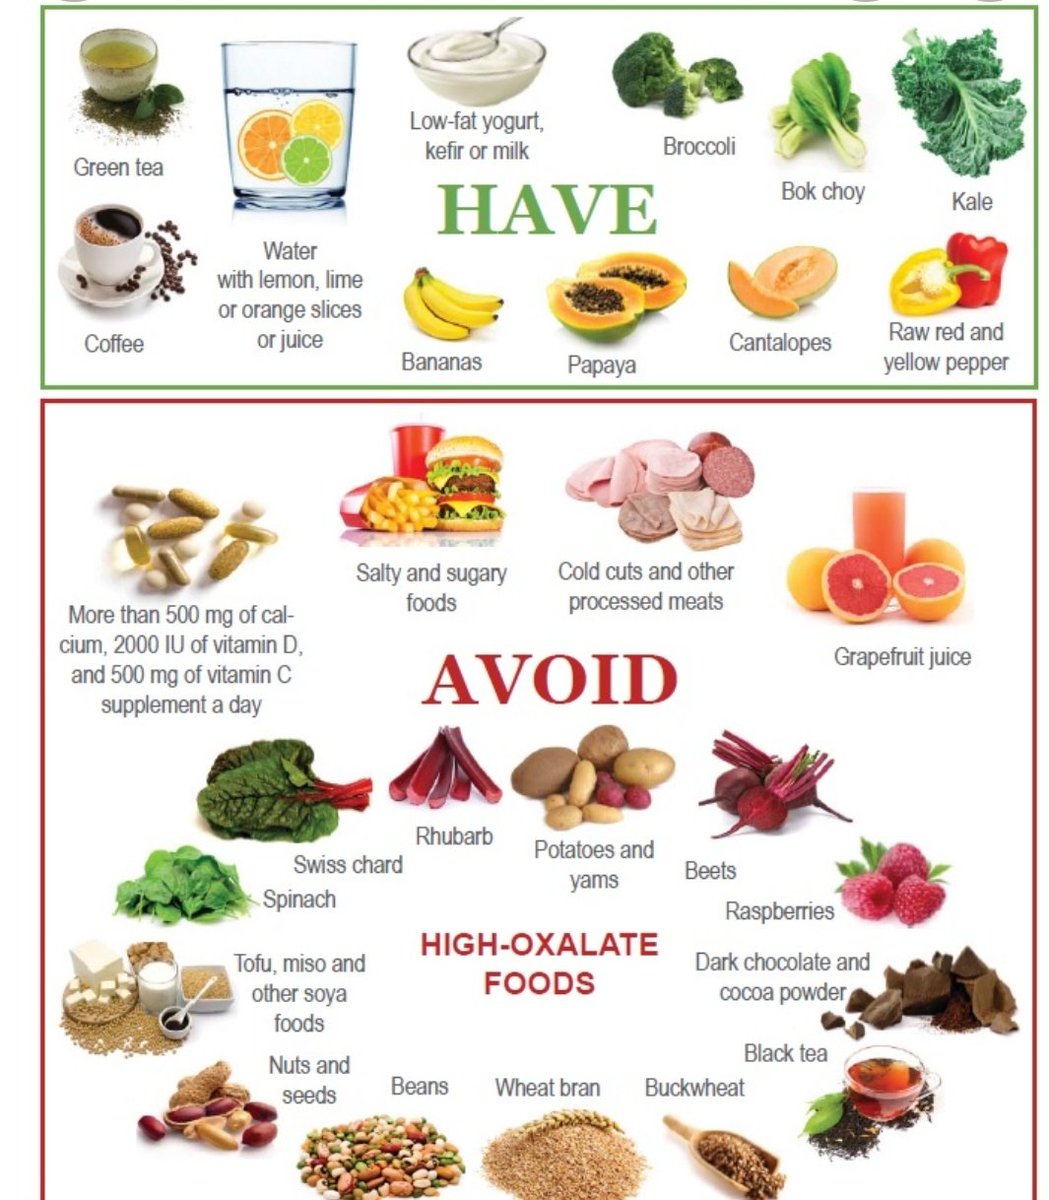

✅طرق الوقاية.

✅طرق الوقاية.